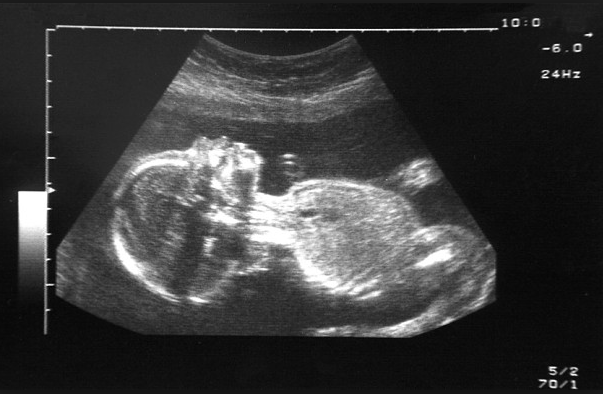

During an ultrasound the sonographer runs a plastic scanner over the mother’s naked belly, and that classic grainy image of the fetus appears on screen. For Anton, this was a romantic opportunity. The hottie held the mouse — ‘She is learning the ropes’ — Anton placed his mitt over hers and together their hands glided over my belly, circling, swooping in the manner of Torvill and Dean. ‘Spine, kidneys…’ Anton whispered lovingly in her right ear, ‘head circumference, abdomen, femur…’ Can we find out the baby’s gender? I asked. Is everything OK? Anton kept schtum. Why do some sonographers stay silent, when every parent they meet looks desperately to them for reassurance?

Anton had three reasons to support his theory. The first was a discrepancy between the baby’s head size (normal) and his stomach (small). The second was a relatively new test, the ‘doppler’ scan of uterine arteries. ‘High resistance,’ said Anton. ‘Baby struggling.’ The third reason was the most surreal: ‘Deep placental legs,’ said Anton. Legs? ‘Yes. Legs.’ Legs? I asked again, pointing to my own.

Anton’s eventual diagnosis, written like a death sentence across our scan notes, was: IUGR. Interuterine growth restriction (early onset). He did mention that only the fetal specialist could make a proper diagnosis, but the specialist wasn’t free for five days. Anton also made it plain he thought our child a write-off. ‘Do you still want to know the sex?’ he said as we fumbled silently into our coats. ‘Still’? Why ‘still’? I stared at him blankly. He shrugged. ‘Boy,’ he said and turned away.

Anton’s mistake, the professor explained, was false certainty. He’d doomed my baby on the basis of measurements he should have seen only as guidelines. ‘Your baby was upside down for the first scan. This means all the measurements get squashed,’ he said. ‘They are not to be trusted.’ Even if the baby had been right way up, the measurements and how they’re interpreted are approximate. The parameters for normality used in most NHS hospitals are based on studies from the 1970s.